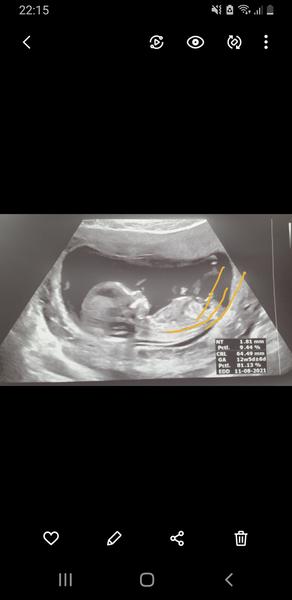

@janagranada zkoušela jsem trochu ten uhel, ale nevim to mam dobre a jestli se to da takto brát.

Holky, co myslíte? Kluk nebo holka? Když si odmyslím bambulku tak vidím kávové zrno. Vidíte ho taky?

Je možné aby byla bambulka pupečník nebo je to kluk jak buk? 🙂)